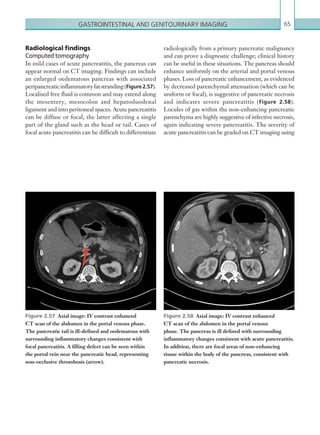

ascending colon and the proximal transverse colon.

The IMA supplies the distal transverse colon, the

descendingcolonandthesigmoidandproximalrectum

(splenic flexure to rectum). The splenic flexure and

rectosigmoid junction are termed ‘watershed areas’ and

are particularly susceptible to ischaemia caused by low-

flow states.

Bowel ischaemia typically affects the middle aged to